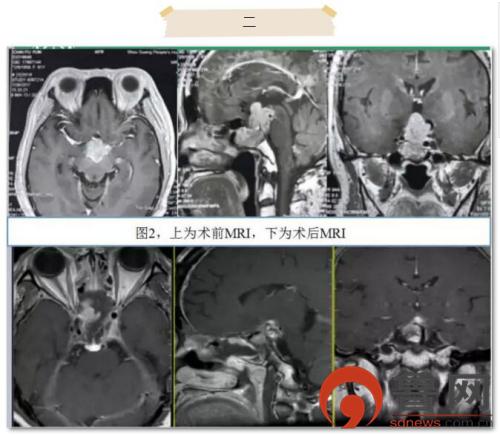

患者2为61岁老年女性,分别于2004年和2016年行两次开颅垂体瘤切除术,此次主诉视力视野障碍来诊。因肿瘤挤压视神经严重,患者入院时几乎失明。患者在院外已行两次开颅手术,此次对再次开颅手术有抵触。术前科室讨论认为肿瘤主要位于鞍上及第三脑室,侵犯脑干,手术的主要难点为打开鞍隔后的脑脊液漏修补及完整切除累及上斜坡的肿瘤。术中采取扩大蝶鞍入路,全切鞍内肿瘤后打开鞍隔,磨除鞍背骨质,保护环窦、基底窦,进一步探查见肿瘤黏连基底动脉、后交通动脉、动眼神经,并与脑干黏连,内镜下切除完全(图2)。后取自体阔筋膜、肌肉、脂肪,联合止血材料和生物蛋白胶使用“三明治”法修补鞍底。麻醉清醒即刻患者诉视力恢复,无神经功能缺失,术后放置腰大池引流2周,拔除后未再出现脑脊液鼻漏,患者顺利出院。